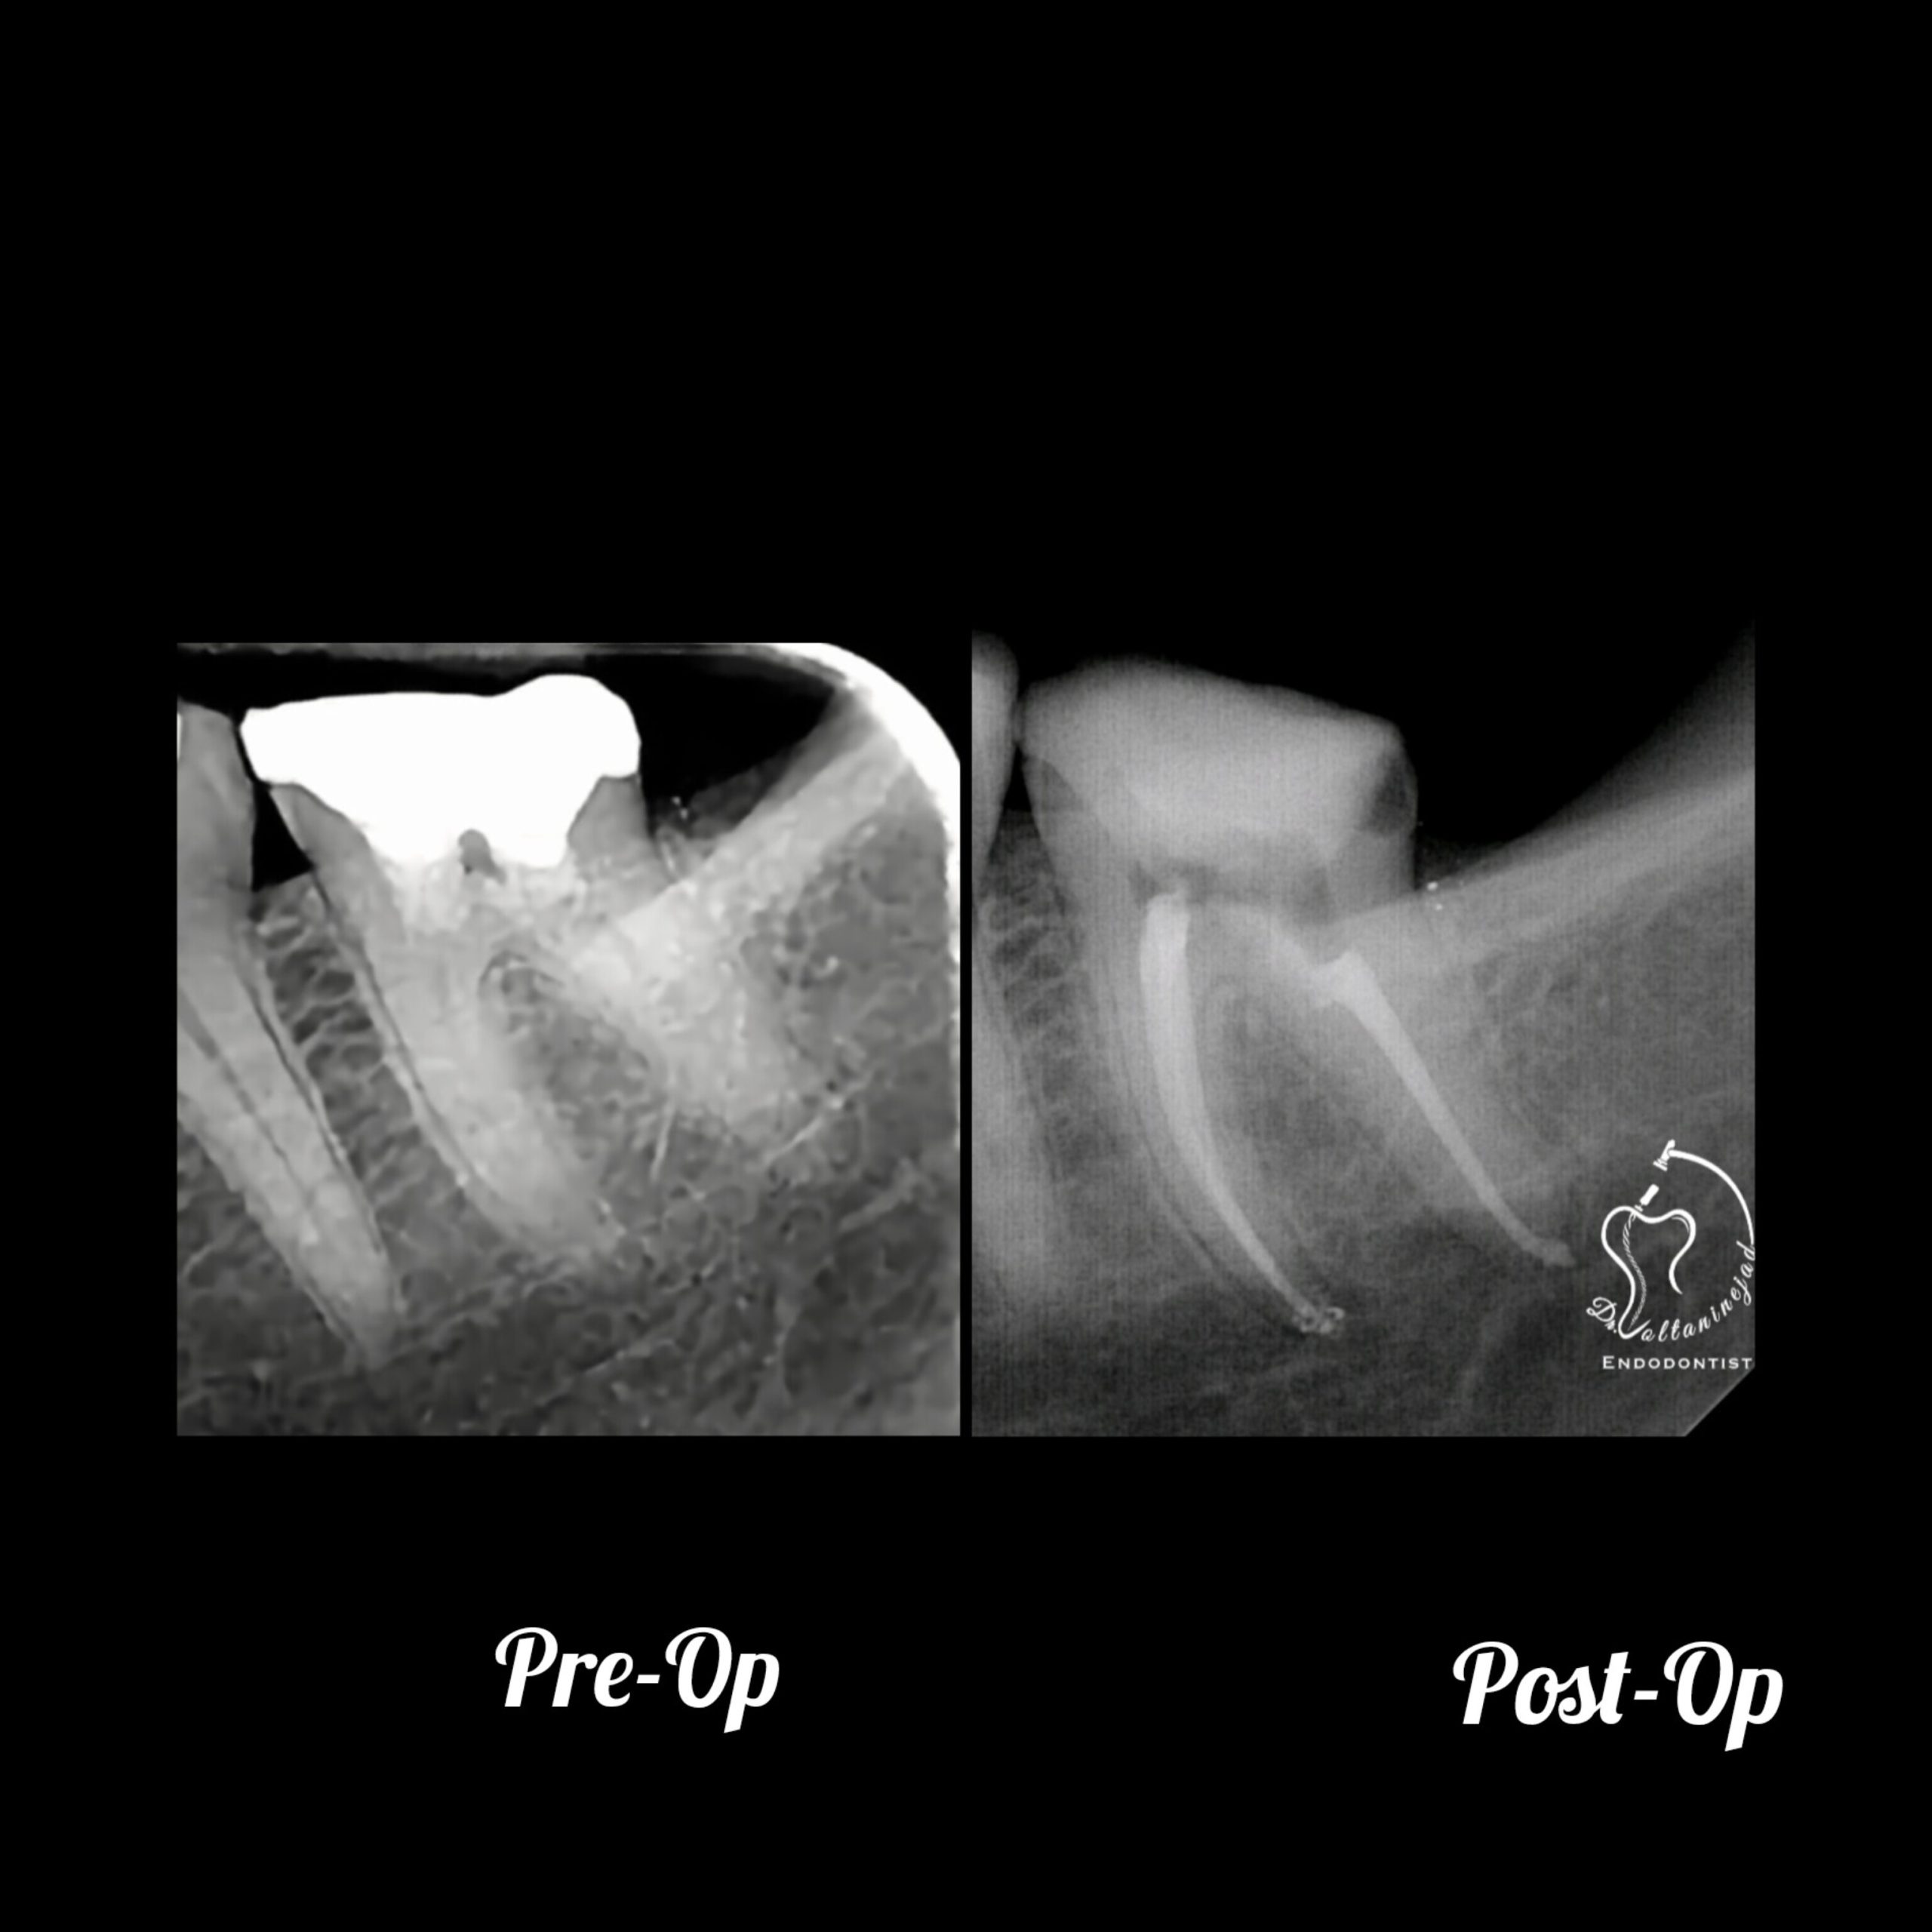

🔹 درمان ریشه مجدد (Retreatment) در دندان پرمولر

• شرح کوتاه: درمان قبلی نامناسب و همراه با عفونت بود. درمان مجدد با میکروسکوپ انجام شد.

• نتیجه: ترمیم ضایعه استخوانی و بازگرداندن دندان به شرایط سالم.

درمان ریشه مجدد پرمولر